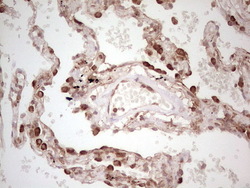

- Submitted by

- OriGene (provider)

- Main image

- Experimental details

- Immunohistochemical staining of paraffin-embedded Human lung tissue within the normal limits using anti-WIBG mouse monoclonal antibody. (Heat-induced epitope retrieval by 1 mM EDTA in 10mM Tris, pH8.5, 120C for 3min, TA806496)

- Validation comment

- IHC